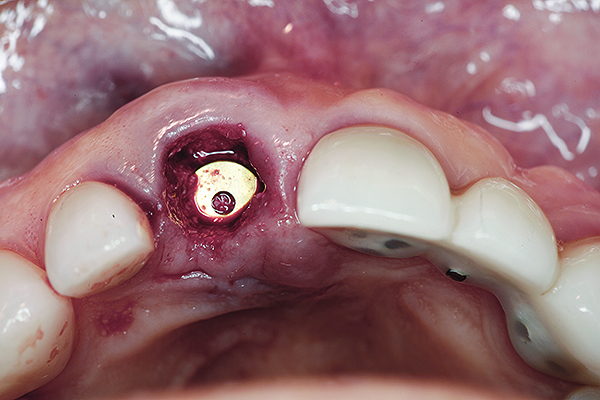

Fig 1. Preoperative clinical photograph of fractured maxillary right central incisor (tooth No. 8).

Figure 1

A 63-year-old female patient presented with mobility of her right maxillary incisor, tooth No. 8, secondary to endodontic therapy (Figure 1). Her medical and dental histories were non-contributory. Clinical and radiographic evaluations revealed an 8-mm probing depth on the palatal aspect. The tooth was deemed to be fractured (Figure 2). The treatment plan accepted by the patient was for extraction, immediate implant placement, and immediate provisional restoration, if possible.

Without reflecting a full-thickness mucoperiosteal flap, the root tip was carefully extracted using periotomes to preserve the buccal plate and interproximal bone (Figure 3 and Figure 4). The extraction site was carefully debrided, and an osteotomy was prepared following the manufacturer’s instructions for placement of a 5/4mm D x 13mm L OSSEOTITE® Tapered Certain® PREVAIL® Implant (BIOMET 3i, www.biomet3i.com).